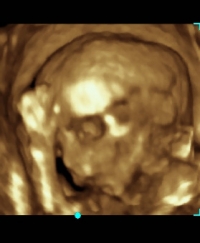

Na tym etapie ciąży szczególnie ciekawe jest badanie w technice trójwymiarowej. Jeżeli tylko warunki techniczne badania są odpowiednie (położenie płodu, odpowiednia ilość wód płodowych), można bardzo dokładnie uwidocznić zarys twarzy płodu, kończyny, płeć. USG ginekologiczne W naszej poradni przeprowadzamy w pełnym zakresie badania USG narządu rodnego, zarówno przezbrzuszne, jak i przezpochwowe.